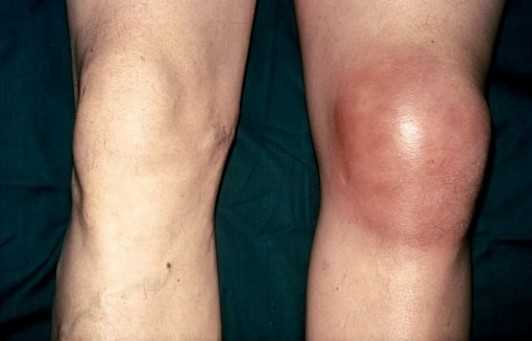

Вид нижней конечности при воспалении синовиальной сумки колена

Клинические проявления зависят от стадии воспаления, при остром состоянии симптомы выражены наиболее ярко. Признаки бурсита коленного сустава включают:

отечность вокруг сочленения, разглаживание кожного рисунка;

снижение амплитуды движений на фоне болевого синдрома и отека;

местное повышение температуры над суставом.